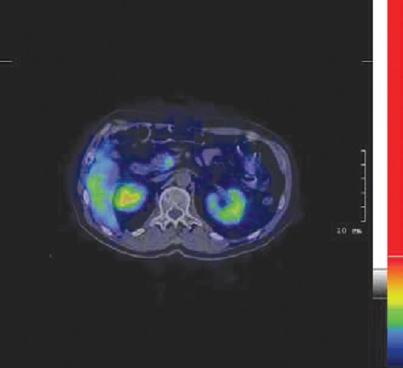

На рис. 7 приведены сцинтиграммы исследования РФЛП 68Ga-DOTATATE для диагностики и контроля эффективности терапии НЭО [25].

Рис. 7. НЭО – ВИПома, синдром Вернера-Моррисона, высокие дозы депо октреотида (Сандостатин ЛАР). После проведения одного цикла с 5 ГБк Y-90 DOTATATE не было показаний к назначению депо октреотида через 3 месяца, увеличение веса на 15 кг, значительное сокращение опухоли (частичная ремиссия). После 1 года наблюдения – нормальная функция печени и почек / Fig. 7. NET – VIPoma, Werner-Morrison syndrome, high doses of octreotide depot (Sandostatin LAR). After one cycle with 5 GBq Y-90 DOTATATE, there was no indication for octreotide depot at 3 months, weight gain of 15 kg, significant tumor reduction (partial remission). After 1 year of observation - normal liver and kidney function